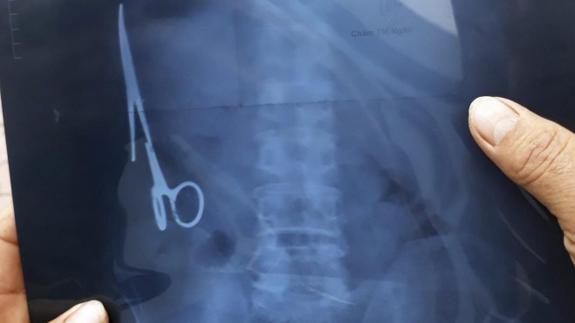

Un vietnamita ha vivido 18 años con unas tijeras que los médicos se olvidaron en su estómago y de cuya presencia nadie se había dado cuenta hasta el mes pasado, cuando sufrió un accidente de tráfico y le hicieron una radiografía.

La intervención quirúrgica para retirar el instrumento médico de 15 centímetros de largo se realizó el sábado pasado en un hospital de la provincia de Thai Nguyen, en el norte de Vietnam, y duró unas tres horas.

Las tijeras se encontraban oxidadas, en la parte izquierda del estómago, según los doctores que el intervinieron citados por el medio vietnamita Tuoi Tre.

El paciente, un hombre de 54 años, nunca había sentido molestias por la presencia de las tijeras que se olvidaron en su estómago en junio de 1988, cuando le intervinieron en el Hospital General Bac Kan por otro accidente de tráfico.